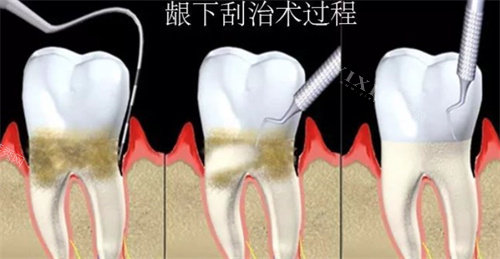

•医生也得看结果再动手。

刮完一部分,医生得瞧瞧牙龈反应怎么样,牙周袋(就是牙齿和牙龈之间加深的“沟”)有没有变浅。

根据情况调整后续计划,比如某个角落可能得返工,加点药。

•中度(地基出现裂缝):牙周袋变深了(大约4-6毫米),牙龈开始萎缩,牙齿容易酸软。

结石已经钻到龈下甚至牙根表面。

全口刮治就得分区域作业,一般3-4次完成一个疗程,这样每次时间适中,你舒服点。

•重度(地基严峻塌陷):牙槽骨吸收明显,牙齿都松动了!结石又硬又多,死死黏在牙根深处,光靠常规刮可能不够,有时还得配合小手术(比如翻瓣)。

总次数4-6次甚至更多很正常,战线可能拉长到几个月。